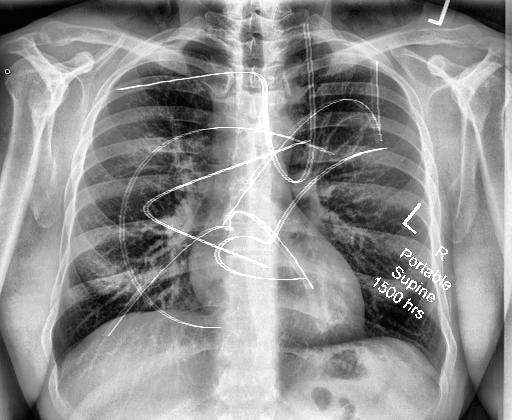

Automated catheter detection is a challenging task. Although most catheters have a radiopaque strip to facilitate detection, the strip may become less apparent depending on the projection angle. Catheters maybe confused by other similar linear structures like ECG leads and anatomy including ribs. Additionally, portions of catheters can be occluded by anatomical structures given that radiographs are a 2D projection of a 3D structure. For example, when a NGT is placed within the oesophagus, the catheter itself becomes less apparent due to the high density of the adjacent vertebrae. Finally, the number and type of catheters that could possibly appear in pediatric X-rays are unknown a priori. The catheters may be intertwined with each other thus making simple line tracing methods fail. Figure 1 gives three sample pediatric X-ray images with some common catheters highlighted in different colors.

To alleviate this annotation problem in catheter detection, we proposed to use X-ray images with simulated catheters by exploiting the fact that catheters are essentially tubular objects with various cross sectional profiles. To be more specific, a synthetic 2D projection of a catheter is generated by first simulating a horizontal catheter profile and then using it as a brush tip to draw along a B-spline path. This generated catheter is then composited with an X-ray image serving as the training data. Another contribution of this work is a segmentation network that can inherently take into account multi-scale information. This network adopts a UNet-style form and contains a recurrent module that can process inputs with increasing scales111Our code is available at https://github.com/xinario/catheter_detection.git.. We have empirically shown that by iterating through the scale space of the input image, higher recall is achieved as compared to using a single scale. Details about the methods are discussed in Section 3. Three sample detection results are shown in Figure 1.

The test dataset is collected locally and only contains frontal chest-abdominal X-rays from patients < 4 weeks old. This is the most common radiograph obtained to confirm placement of catheters such as UACs and UVCs in neonates. Currently, the test set has 35 fully labeled images with different catheter types with sample images previously shown in Figure 1. All the annotated catheters (lines excluding ECG leads) are treated as the same class in the detection.